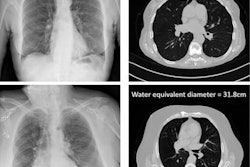

The school has invested in a digital x-ray room, a mobile x-ray system, an ultrasound scanner, a dual-energy x-ray absorptiometry bone density scanner with an image reporting hub, and more. Siemens Healthineers has worked with Coventry to ensure the facilities replicate a hospital setting.